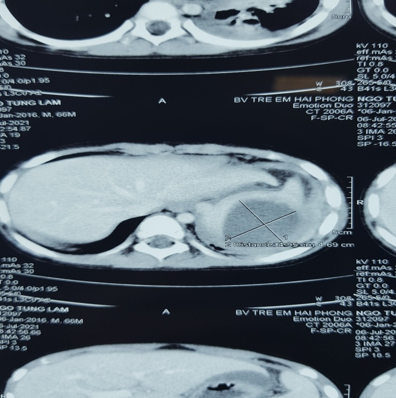

Hình

ảnh ổ abces lách trên phim chụp cắt lớp vi tính (đánh dấu X)